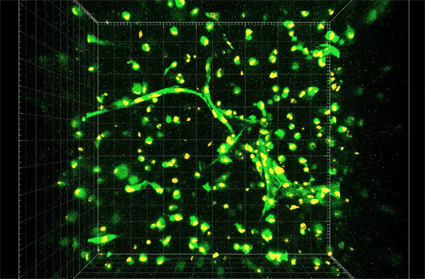

Researchers are closer to working capillaries in 3D-printed organs By Mallory Locklear From engadget A new method allows patient-specific cells to form capillary-like tubes. Researchers have brought 3D-printed organ and tissue capabilities a long way, but the technology still faces…